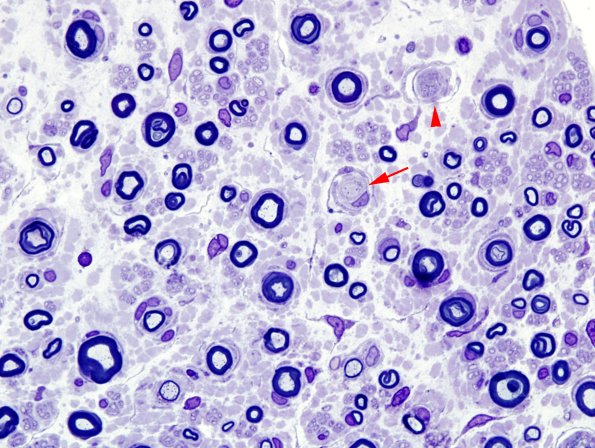

Case 14 No History ---- 14A1 This sural nerve shows numerous demyelinated axons (arrow) and early onion-bulb formations (arrowhead). (Plastic sections)